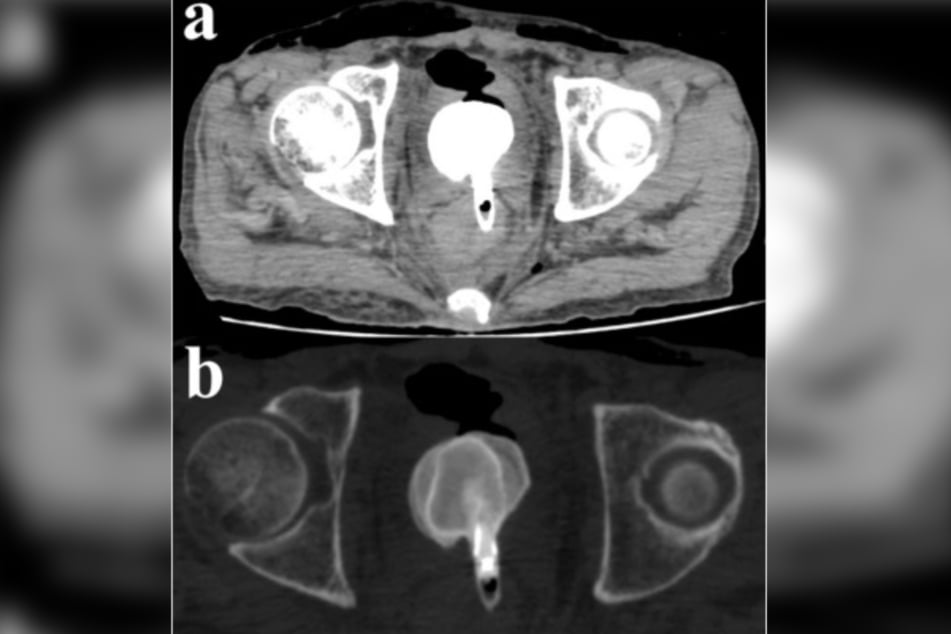

Nachdem er dann in Ohnmacht gefallen war, wurde er in ein Krankenhaus eingeliefert, wo Ärzte zwei Tage lang vergeblich um sein Leben kämpften. Eine Computertomografie zeigte dabei einen Fremdkörper in der Nähe seines Rektums. Worum es sich dabei genau handelte, zeigte erst die Obduktion nach seinem Ableben:

Ein fassungsloser Gerichtsmediziner fand laut einem Bericht von "ScienceDirect" einen Aluminium-Kajalstift im After des Toten. Am neun Zentimeter langen Stift hatte sich ein massiver Blasenstein mit einem Ausmaß von 6,5 Zentimeter x 6 Zentimeter x 4 Zentimeter gebildet.

Dies geschah, da sich der Fremdkörper durch die Vorderwand des Rektums und die Hinterwand der Blase des Mannes gebohrt hatte. Zudem war eine der Nieren geschwollen und gerötet, die Milz vergrößert und seine Harnleiter gedehnt.